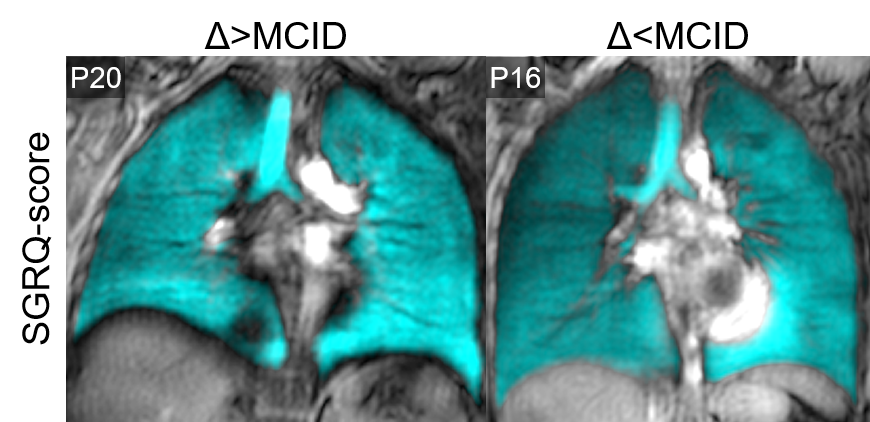

Table 1 provides demographic and imaging characteristics for PACS participants, where 68% experienced a change >MCID in SGRQ-score. Figure 1 shows 129Xe MRI for representative participants in each group, where ventilation is qualitatively similar. Table 2 provides a summary of the best model performances for predicting improvement in SGRQ-score≥4 points, where a weighted K-nearest neighbours (KNN) model exclusively trained on MRI texture features was the best performer (AUC=0.91) and outperformed models trained on clinical measures (AUC=0.75). Figure 2 shows that, of the features in the MRI-model, ΔSGRQ significantly related to original shape maximum 3D diameter (ρ=.39, p=.02) and minor axis length (ρ=.47, p=.005).

Figure 1. Qualitative comparison of 129Xe MRI participants who experienced a change >MCID and <MCID in SGRQ-score between 3- and 15-months post-infection. P20 is a 36-year-old female with 3-/15-month SGRQ-score=18/8 and VDP=2/2%. P16 is a 29-year-old female with 3-/15-month SGRQ-score=23/25 and VDP=1/0%.